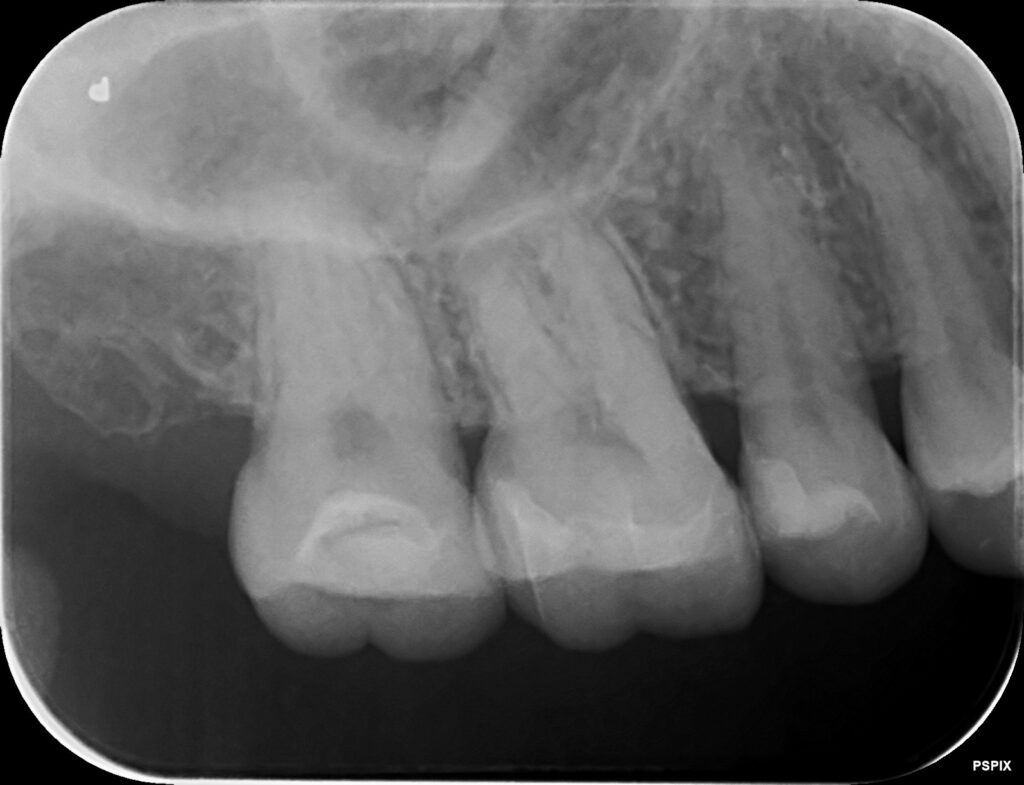

後日セラミックがセットされた状態です。

綺麗にセラミックがセットされました。治療した個所が分からないくらいに仕上がりましたね。

術前と術後です。

エックス線写真も比較してみてみましょう。

しっかりと密閉され、歯と一体型になっているのがわかります。他の歯にみられる、セラミックとのつなぎ目も見られません。この状態だとしっかりと接着され安心となります。